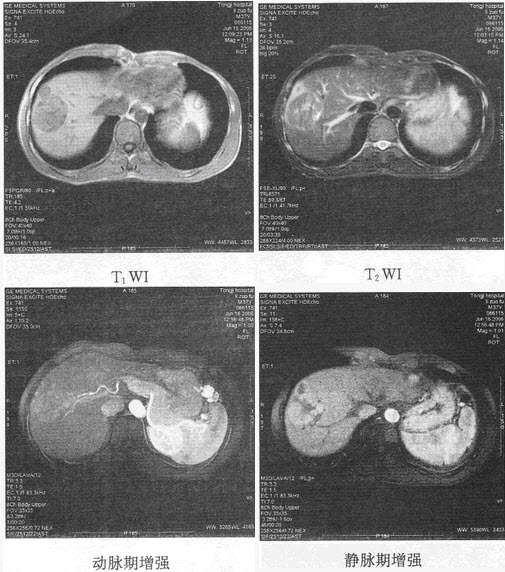

- 单项选择题患者男,54岁。体检发现肝脏占位,MR图像如下,最有可能的诊断是()

- D